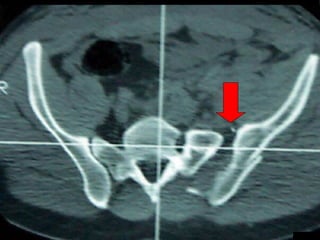

Tc pre op

La lesione dell’apparato muscolo scheletrico che richiede  in ogni caso  un trattamento chirurgico con  priorità   assoluta  è la rottura dell’anello pelvico , che comporta una emorragia severa nel retro peritoneo e nella cavità peritoneale.

Immediata riduzione e fissazione del bacino

Se la risposta emodinamica a questo trattamento è buona il paziente verrà monitorato e potrà essere programmato un successivo intervento di osteosintesi definitiva

Angiografia e/o packing pelvico Se il paziente rimane instabile